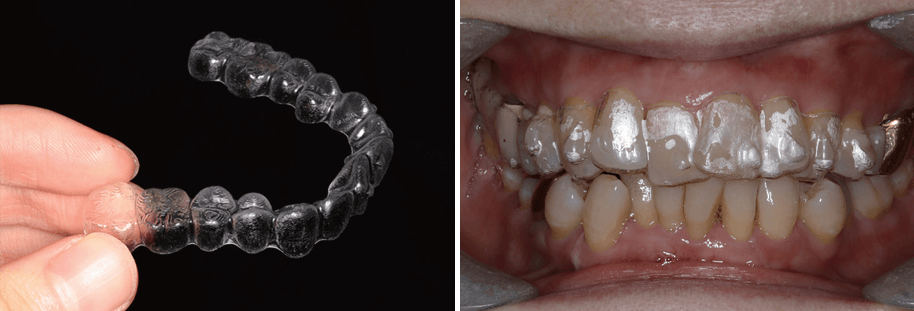

요즘에는 눈에 잘 띄지 않고 불편함을 최소화한 교정장치들이 다양하게 개발되어 힘들지 않게 교정치료를 받을 수 있습니다. 중장년 교정치료 시 사용되는 장치는 크기가 좁쌀보다도 작습니다. 또 탈착이 가능한 투명한 장치도 있는데, 매우 심미적이고 이물감이 적다는 게 장점입니다.

투명장치를 이용한 틀어진 앞니 교정